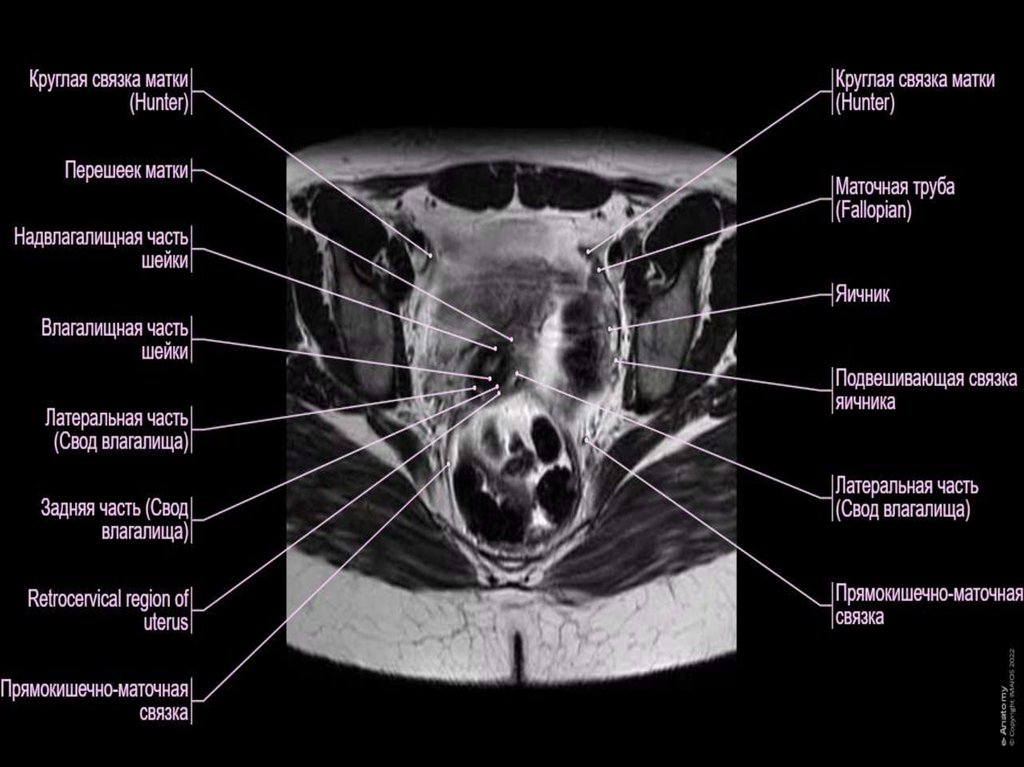

4. Связочный аппарат матки

• Связки матки разделяют на две группы –

подвешивающие и фиксирующие. Первые

соединяют матку со стенками таза, вторые

– оставляют в определенном положении.

6. Подвешивающие связки матки и придатков представлены парными связками, которые соединяют органы друг с другом и стенками малого

Подвешивающие связки матки и придатков

представлены парными связками, которые

соединяют органы друг с другом и стенками

малого таза:

• Широкая связка матки. Это – поперечная складка брюшины. Она

покрывает тело матки и маточные трубы и образует их серозную

(наружную) оболочку. Широкие связки отходят справа и слева к

боковым стенкам таза и переходят в париетальную (пристеночную)

брюшину. На задней поверхности этой связки крепятся яичники.

• Поддерживающая связка яичника. Это – наружная часть широкой

связки матки. Она идет от яичника к ампулярной части маточной

трубы и переходит на стенку таза. Эта связка очень прочная, ведь в

ней проходят питающие яичник сосуды.

• Собственная связка яичника. Проходит в заднем листе широкой

связки – между яичником и маткой. В ней расположены яичниковые

ветви маточных артерий и вены – и поэтому эта связка также

отличается повышенной прочностью.

• Круглая связка матки. Это относительно тонкий канатик, состоящий из

гладких мышц и соединительной ткани. Достигает величины 10-15 см.

Начинается от углов матки и идет под широкой связкой в паховый

канал, а далее – разветвляется в толще половых губ.

11. Фиксирующие связки представлены такими элементами:

• Поперечная связка матки. Ее также называют

главной. Окружает шейку матки на уровне

внутреннего зева. Вплетается в тазовую фасцию и

фиксирует матку в определенном положении к

тазовому дну.

• Пузырно-маточные и лобково-пузырные связки.

Протянуты от матки к мочевому пузырю и лобку.

• Крестцово-маточные связки. Начинаются от задней

поверхности матки чуть ниже ее внутреннего зева,

охватывают с двух сторон прямую кишку и

вливаются в тазовую фасцию на уровне крестца.